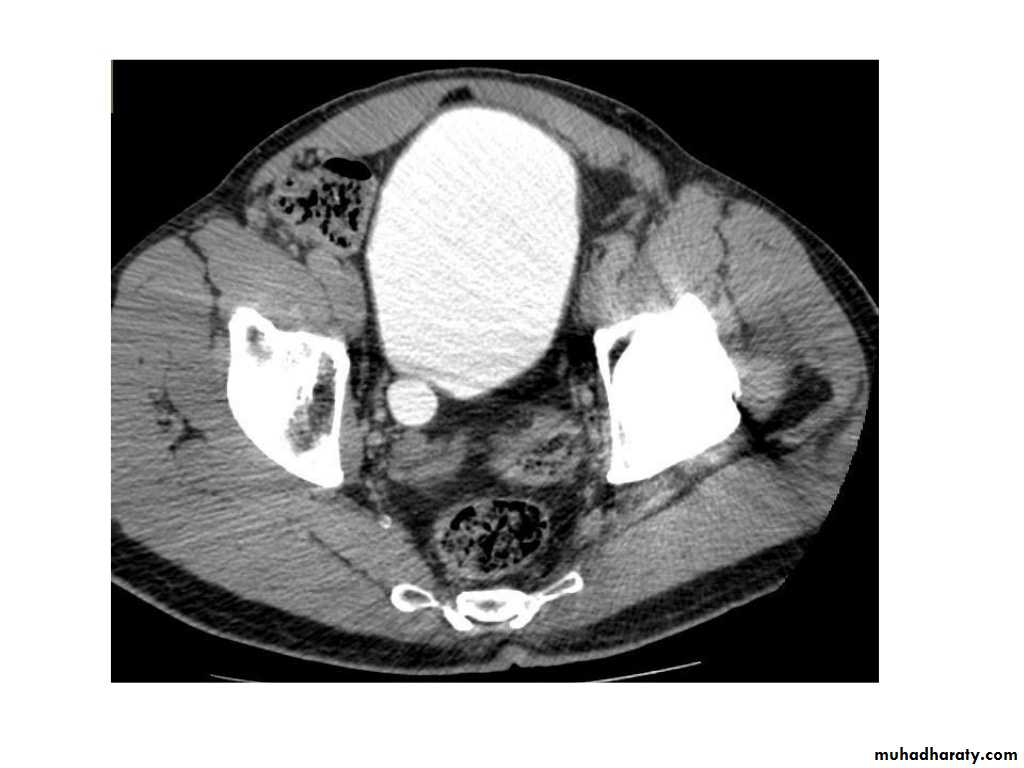

IVU shows

1. The kidneys at low position .2.Close to the spine with long axis parallel to the spine

3. Malrotation manifested by medially directed calyces.

4- The renal pelvis and ureters are anterior and lateral in position.

5- Hydronephrosis and calculi highly associated.